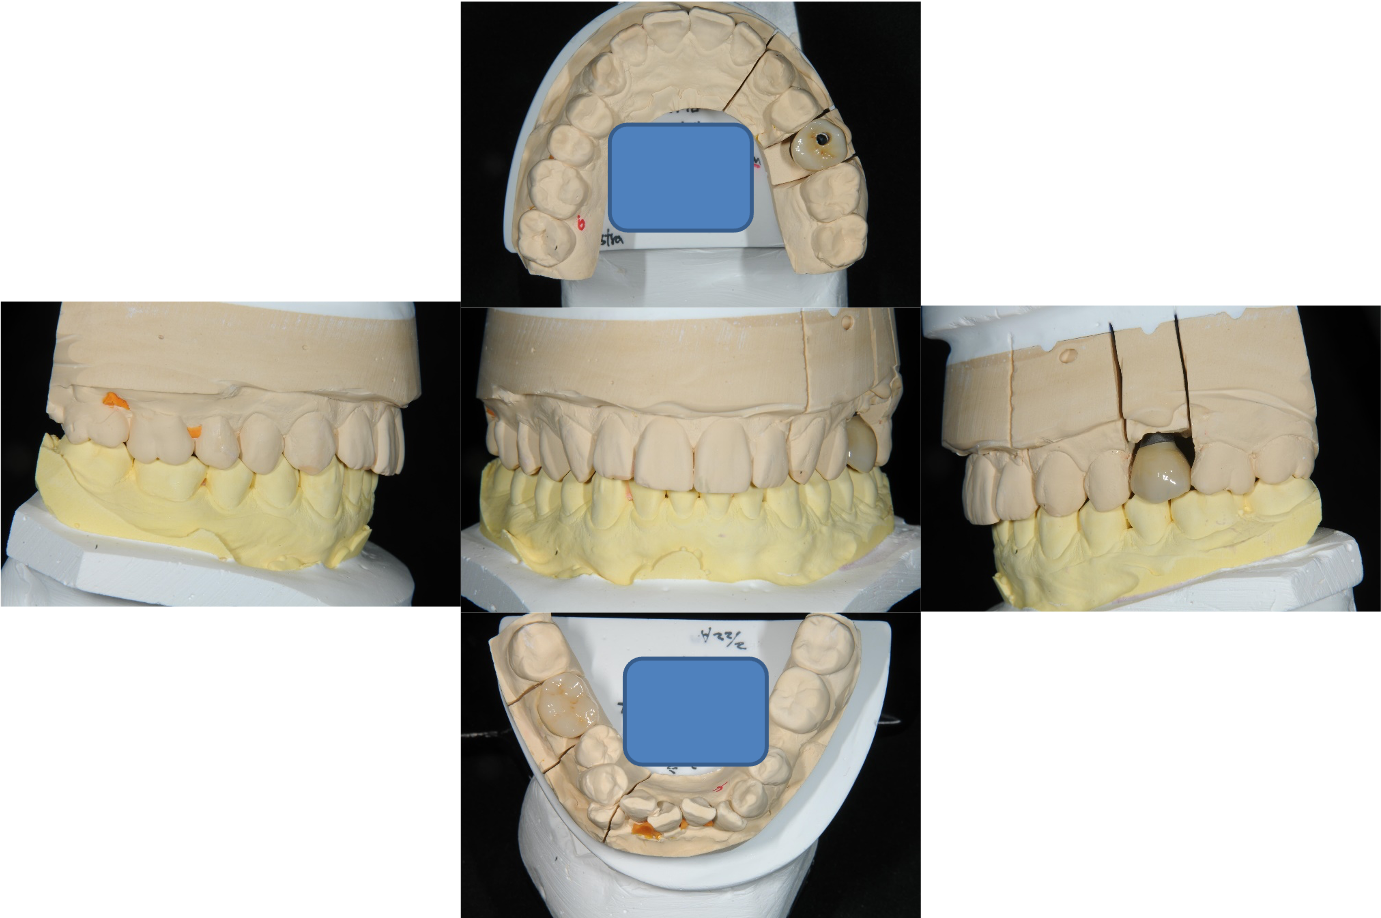

上面弓與咬合器

咬合器上製作假牙